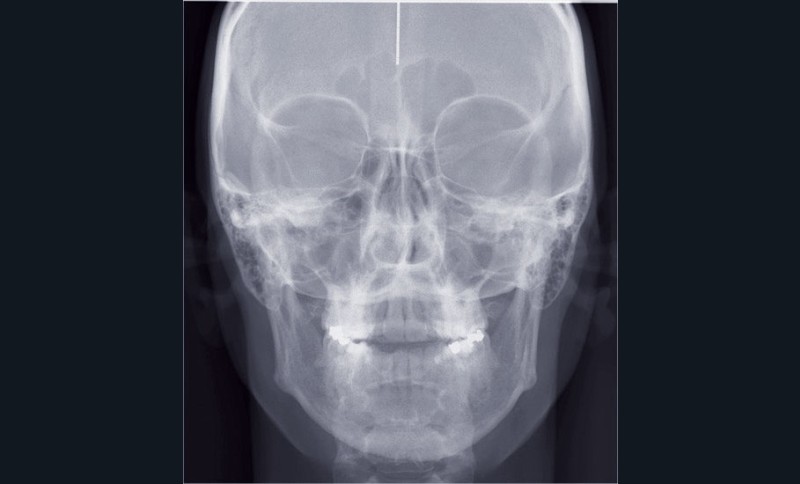

Cas n° 1

Il a été décidé de mettre en œuvre une thérapeutique avec brackets vestibulaires Damon afin d’optimiser l’expansion des arcades, la fermeture de la béance et la réduction du sourire gingival latéral qui perturbe l’esthétique du sourire de la patiente.

La patiente demande des attaches céramiques et nous trouvons un compromis en lui proposant un appareillage Insignia Damon Clear au maxillaire et Damon métallique à la mandibule.